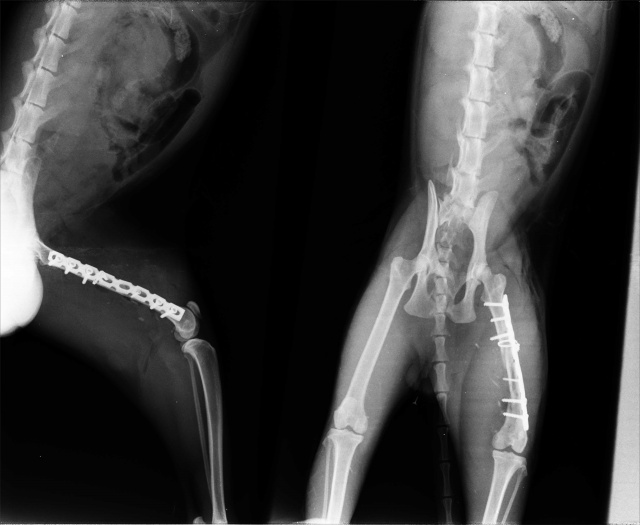

- Множественный оскольчатый перелом бедра

27.11.2014 - остеосинтез бедренной кости.